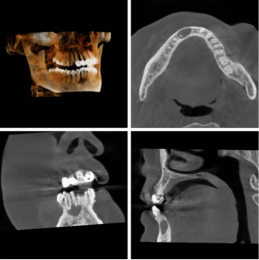

迷失自我的牙齿

隐匿性口腔问题的探测神器——口腔CBCT